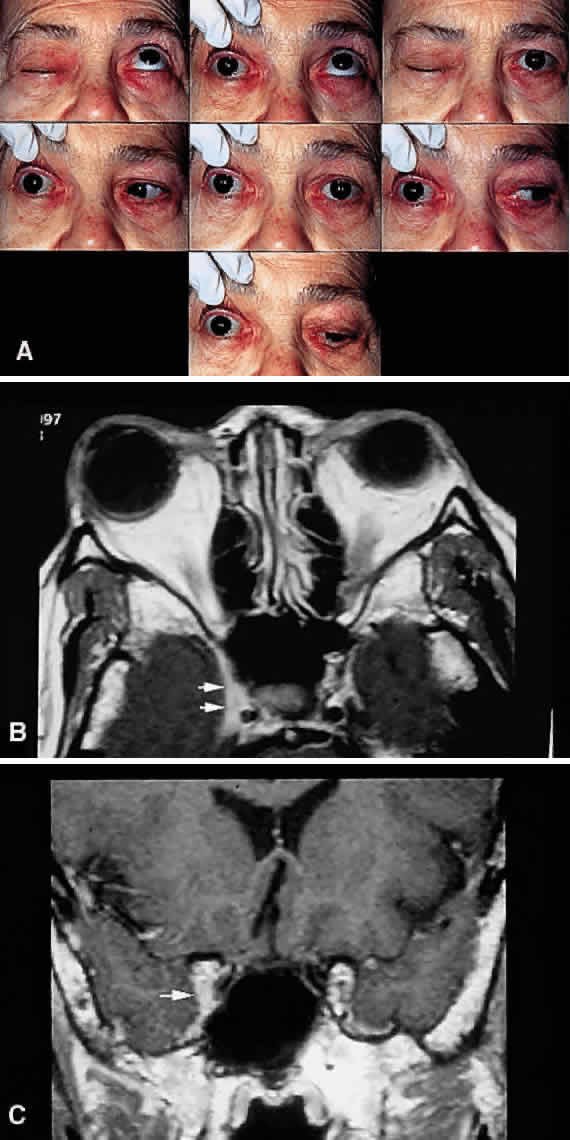

Second, the motor fibers to the EOMs usually enter the inner aspect of each muscle at the junction of the posterior one third and the anterior two thirds of the muscle's length. The exception is the nerve to the inferior oblique, which runs along the lateral aspect of the inferior rectus muscle to enter the inferior oblique muscle near the globe's equator (see Fig. 14). This nerve may be damaged with manipulation of inferior orbital soft tissue during repair of an orbital floor fracture. Because the parasympathetic fibers of the pupil also travel with the nerve to the inferior oblique at the orbital apex, any anterior traction may cause contusion to these more posterior fibers, resulting in a postoperative Adie's pupil.14 VASCULAR SUPPLY Arteries The tissues of the orbit and periorbital region derive their blood supply from two sources—the internal and external carotid arteries.15 Although the majority of orbital blood supply comes from the ICA, anastomoses with external carotid supply are numerous. The ICA enters the calvarium through the foramen lacerum, runs near the posterior clinoid process, and then makes a sharp turn to enter the CS with the abducens nerve (see Fig. 13). As already noted, within the CS the ICA has an S-shaped course called the carotid siphon. As the ICA exits the CS, it gives off its first major intracranial branch, the ophthalmic artery. Before giving off the ophthalmic artery, the ICA has several minor branches that supply the meninges, including the dura of the lateral wall of the CS. An abnormal communication between the arterial and venous supply of the CS results in either a carotid-cavernous fistula or a dural-sinus fistula (Fig. 18A). Because of the larger caliber of the ICA, a carotid-cavernous fistula is usually symptomatic secondary to a high flow state, possibly manifesting as orbital/ocular ischemia and increased intraocular pressure. This type of fistula is most commonly encountered in younger patients after blunt trauma and may require invasive neuroradiologic treatment (Fig. 18B). Conversely, a dural-sinus fistula is typically a low-flow state because the abnormal communication forms between the small-caliber dural arterial feeders of the lateral CS wall and the venous plexus of the CS. Such fistulas are usually seen in older individuals as a spontaneous event. Depending on the severity of symptoms, most dural sinus fistulas are simply followed by observation because of the high rate of spontaneous closure. The ophthalmic artery enters the optic canal inferolateral to the optic nerve, carrying with it a sympathetic plexus from the ICA. The intraorbital course of the ophthalmic artery is highly variable. In about 83% of cases, the artery crosses over the optic canal from lateral to medial and continues to travel superomedially in the orbit to its terminal branches. While still within the orbit, the ophthalmic artery gives off several branches.16 These are most easily subdivided into three groups: ocular, muscular, and extraorbital (Table 12, Fig. 19).